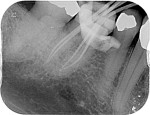

Root canal treatment can be a difficult procedure for the dentist to perform to the internal complexity of the canal system.

On the second appointment we do the same procedure with local anaesthetic and disinfect and prepare the canals, once we are happy with our preparation the canals are sealed with rubber points and a sealant into each canal. Radiographs may be taken to check our progress before sealing. A temporary restoration may be placed depending if the tooth requires further treatment.

A follow up x-rays is normally taken a year after completion to ensure any areas of infection are healing.